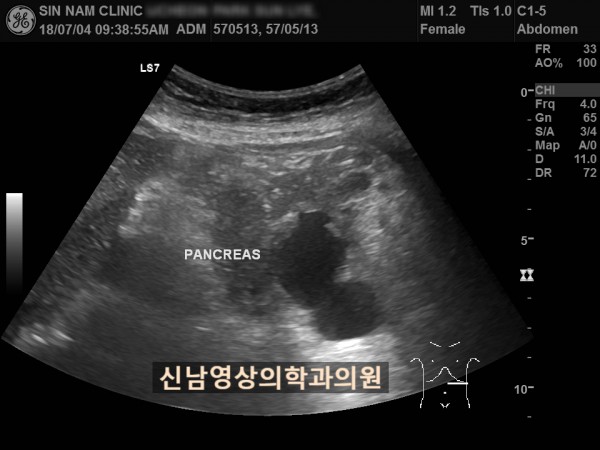

아래 환자분은 60대 여성분으로 식사만 하면 복통이 나타나서 내과에서 위 / 대장 내시경을 받으셨지만 정상으로 진단받았던 분으로 내과에서 복부 초음파검사를 했지만 이상 소견을 발견하지 못했던 분입니다.

복부 초음파 검사상 췌장꼬리(미부)에서 발생한 암으로 대장 장간막으로 전이가 되어서 대장내시경에서는 정상으로 확인되었고, 식사를 하면 장간막 전이때문에 장폐색 증상으로 복통이 발생하셨던 것으로 복막으로 전이가 진행되어 복수까지 있었습니다.